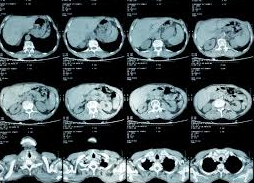

A complete history and physical examination are necessary for early diagnosis and treatment. X-ray; magnetic resonance imaging (MRI); computed tomography (CT) scan; ultrasonography; blood studies; tumor markers; tissue biopsy and tumor staging may be required.